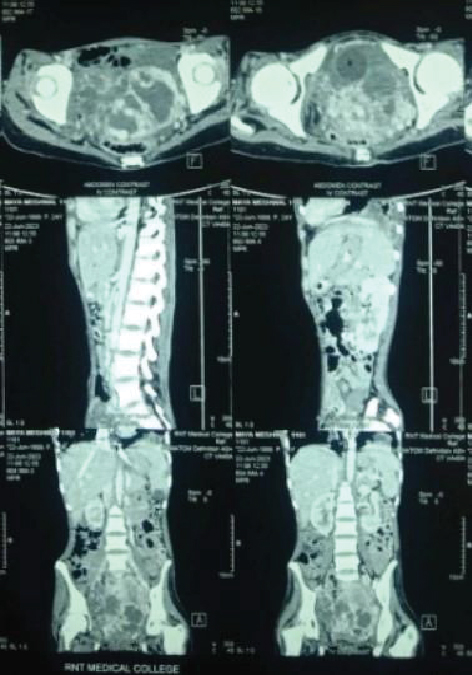

She was started on steroids, 5 units of blood were transfused with inotropic support and as the patient’s condition improved a contrast-enhanced computed tomography (CECT) thorax and abdomen was planned. Heterogeneously enhancing soft tissue mass in pelvic cavity with nonseparate visualization of bilateral adnexa with multiple heterogeneous opacities of varying sizes in both lung fields were visualized (Figs. 5 and 6). Serum beta-hCG was sent immediately, which was found to be elevated to 10,000 mIU/mL. However, CA-125 and alpha fetoprotein (AFP) levels were within normal limits.

Figure 6. CECT abdomen and pelvis showing heterogeneously enhancing soft tissue density mass in pelvic cavity with nonseparate visualization of bilateral adnexa.